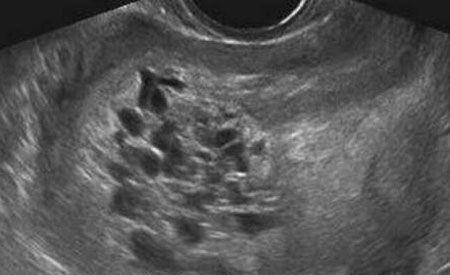

河南驻马店关某5个月前被查出怀孕,虽然是满心欢喜但是她却嫌做产检麻烦,除了确诊怀孕那天到过医院,其余时间5个月内再无涉足入医院半步。直到某天她腹部突然剧痛难忍,家人把她紧急送院,做了彩超检查后众人大惊失色,医生说她的肚子里根本看不到宝宝,只能看到一些类似蝌蚪状的小生物。后来医生经过精细检查,才诊断出关某的情况为葡萄胎,因受精卵异常所致,出现类似“葡萄”“小蝌蚪”等形态的小细胞。

你听过的产子最高数量是多少个呢,5个?8个?或者是一支足球队的人数?其实在我国古代曾有妇女产子六百的记录,后来人们才发现这数据不真实,不是数量上含水分,而是生出的这些怪胎全部是因为妊娠后胎盘绒毛滋养细胞增生、间质水肿因而导致出现大小不同的水泡,他们被称为是“奇胎”或“水泡状胎块”,因看上去像一串串葡萄,现医学名称其为“葡萄胎”。2、葡萄胎分类随着科学家对其研究深入,葡萄胎现被分为两类:(一)完全性葡萄胎胎盘绒毛全部受累,整个宫腔充满水泡,弥漫性滋养细胞增生,无胎儿及胚胎组织可见;(二)部分性葡萄胎部分胎盘绒毛肿胀变性,局部滋养细胞增生,胚胎及胎儿组织可见,但胎儿多死亡,有时可见较孕龄小的活胎或畸胎,极少有足月婴诞生。